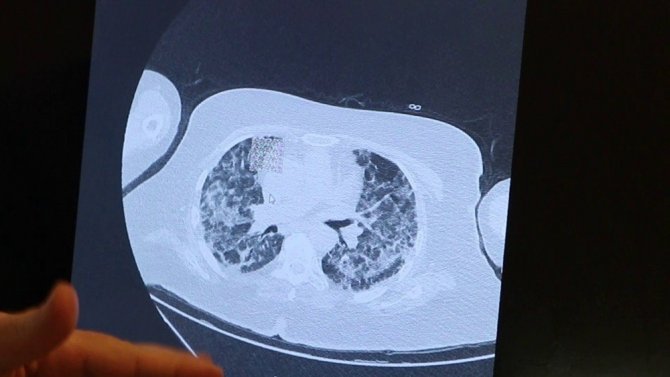

Farklı aileden yaşları yüksek olan 4 kişinin akciğer tomografilerini de inceleyen Prof. Dr. Şevket Özkaya genellikle hastaların akciğerlerinin hava yerine bir sıvı ile dolduğunu belirterek, "Biz mart-nisan aylarından sonra Türkiye'de korona virüs vakalarının ilk olduğu dönemlerde genelde her ailede bir kişinin enfekte olduğunu görüyorduk. Onu kontrol altına almaya çalışıyorduk. Oysa son 3-4 aydır ailedeki bir kişinin bütün aile fertlerini enfekte ettiğini ve en az 5 ile 10 kişilik bir ailede herkesin enfekte olduğunu görüyoruz. Bu kişilerin en az 1-2 tanesinin özellikle yaşlı kişileri yoğun bakıma düşürecek kadar zatürre olduğunu gördük" dedi.

"Tomografilerde yaygın buzlu camlar ve sıvı"

Farklı ailelerden 4 kişinin akciğer tomografilerine bakan Prof. Dr. Özkaya, "82 yaşındaki 4 çocuğu da korona virüse yakalanmış bir hastanın filmine bakarsak, akciğerlerinde yaygın pnönomoni olduğunu görüyoruz. Bu kişi yoğun bakımda tedavi altına alındı. Artık eskisi gibi ailede tek tük enfektelere bakmıyoruz. Ailenin tamamı enfekte oluyor ve özellikle yaşlıları çok ciddi zatürreye döndürecek klinik durumlarla karşılaşıyoruz. 58 yaşında genç bir annenin akciğerlerine bakıyoruz. 3 çocuğunun hepsi ve eşi de enfekte olmuş. Ailede bir kişi enfekte olunca hepsini enfekte etmiş. Maalesef içlerinde immün direnci en düşük olan ve yaşı en büyük olanın akciğerleri solunum yetmezliğine gidecek şekildedir. Her iki akciğerinde de yaygın infiltrasyonla tedavi veriyoruz. Hasta hayati tehlikeyi atlattı. 63 yaşında bir hastanın akciğerlerini inceliyoruz. 63 yaşındaki bu anne yaşıyor ama bu kişilerinin anneannelerini ve babaannelerini Kovid-19 dolayısıyla kaybettik" diye konuştu.